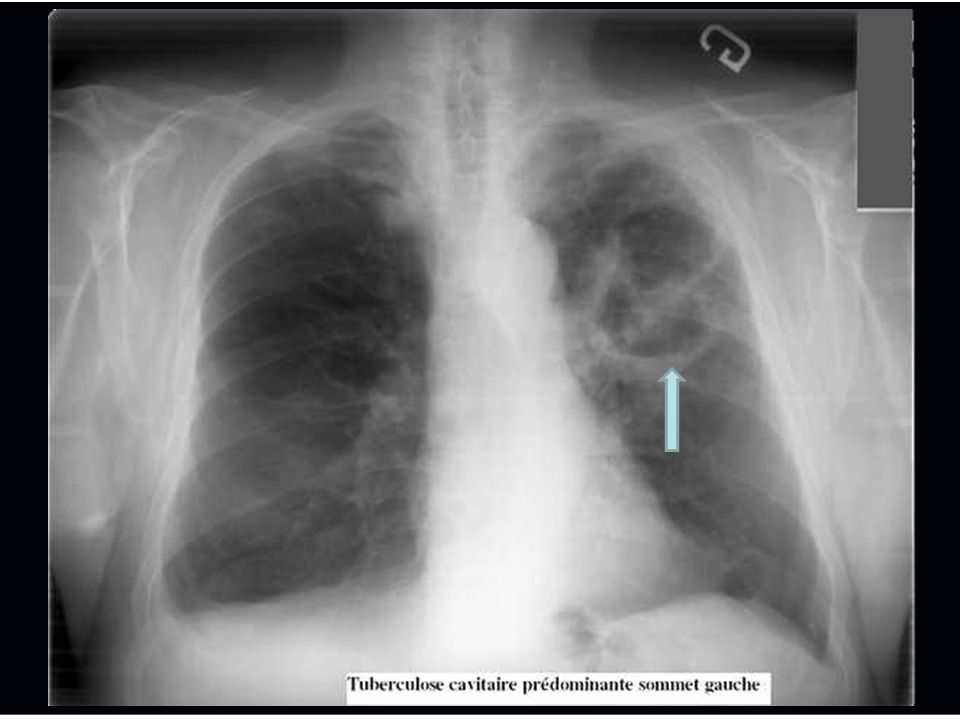

Como identificar a tuberculose no raio-x?

O diagnóstico por imagem é iniciado por avaliação do Raio-X, que deve ser solicitado para todo paciente com suspeita clínica de Tuberculose Pulmonar após a anamnese e exame físico. Essa solicitação tem por objetivo fazer a exclusão de outros diagnósticos diferenciais, avaliar a extensão do acometimento da doença e acompanhar a evolução do tratamento. Alguns achados suspeitos de no Raio-X são as cavidades, nódulos, consolidações, massas, derrame pleural e alargamento do mediastino.